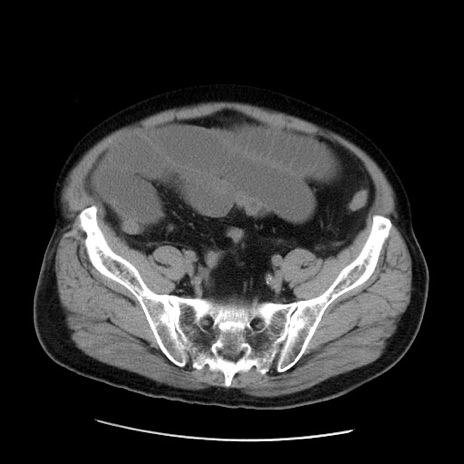

症例20(横断像)

【症例】 60歳代男性

【主訴】 腹部膨満、嘔吐

【現病歴】5日前頃より倦怠感を認め食事量減少し4日前の朝嘔吐、食事摂取困難となった。 3日前近医受診し点滴施行され整腸剤などを処方された。 当日他院を受診し、腹部膨満著明、炎症反応の上昇(CRP10.8、WBC11200)あり、紹介受診となる。

【身体所見】 意識JCS1 受け答えがはっきりしないBP 111/57mHg、 P 67bpm、、BT35.2°C、SpO2 97%(RA)、 腹部:膨隆、打診で鼓音あり、全体的に圧痛有り、腸蠕動音(-)、反跳痛ははっきりせず。

【データ】WBC 11400、CRP 14.20